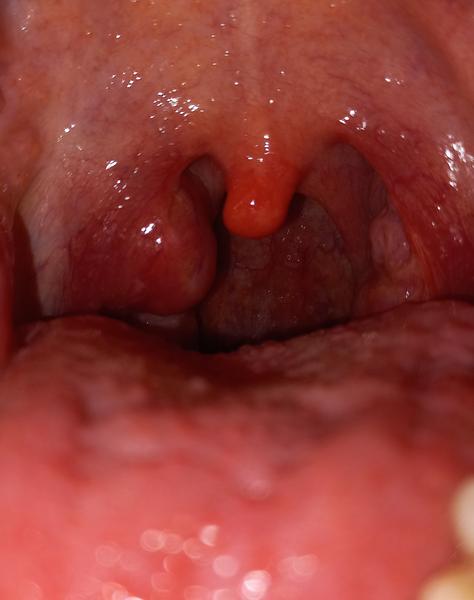

Dobrý večer, jdu si k vám pro radu. Cca před 2 měsíci se mi udělali čepy v ústech (chřipka). Poté to celkem splasklo. Dnes ráno jsem se vzbudila a v ústech jsem našla tohle vz foto. Nevíte co by to mohlo být? V krku a nic jiného mě nebolí. 🤔 vím, že nejlepší bude dr. ale jen se předběžně ptám, jestli se s tím nikdo nesetkal. Děkuji za odpovědi